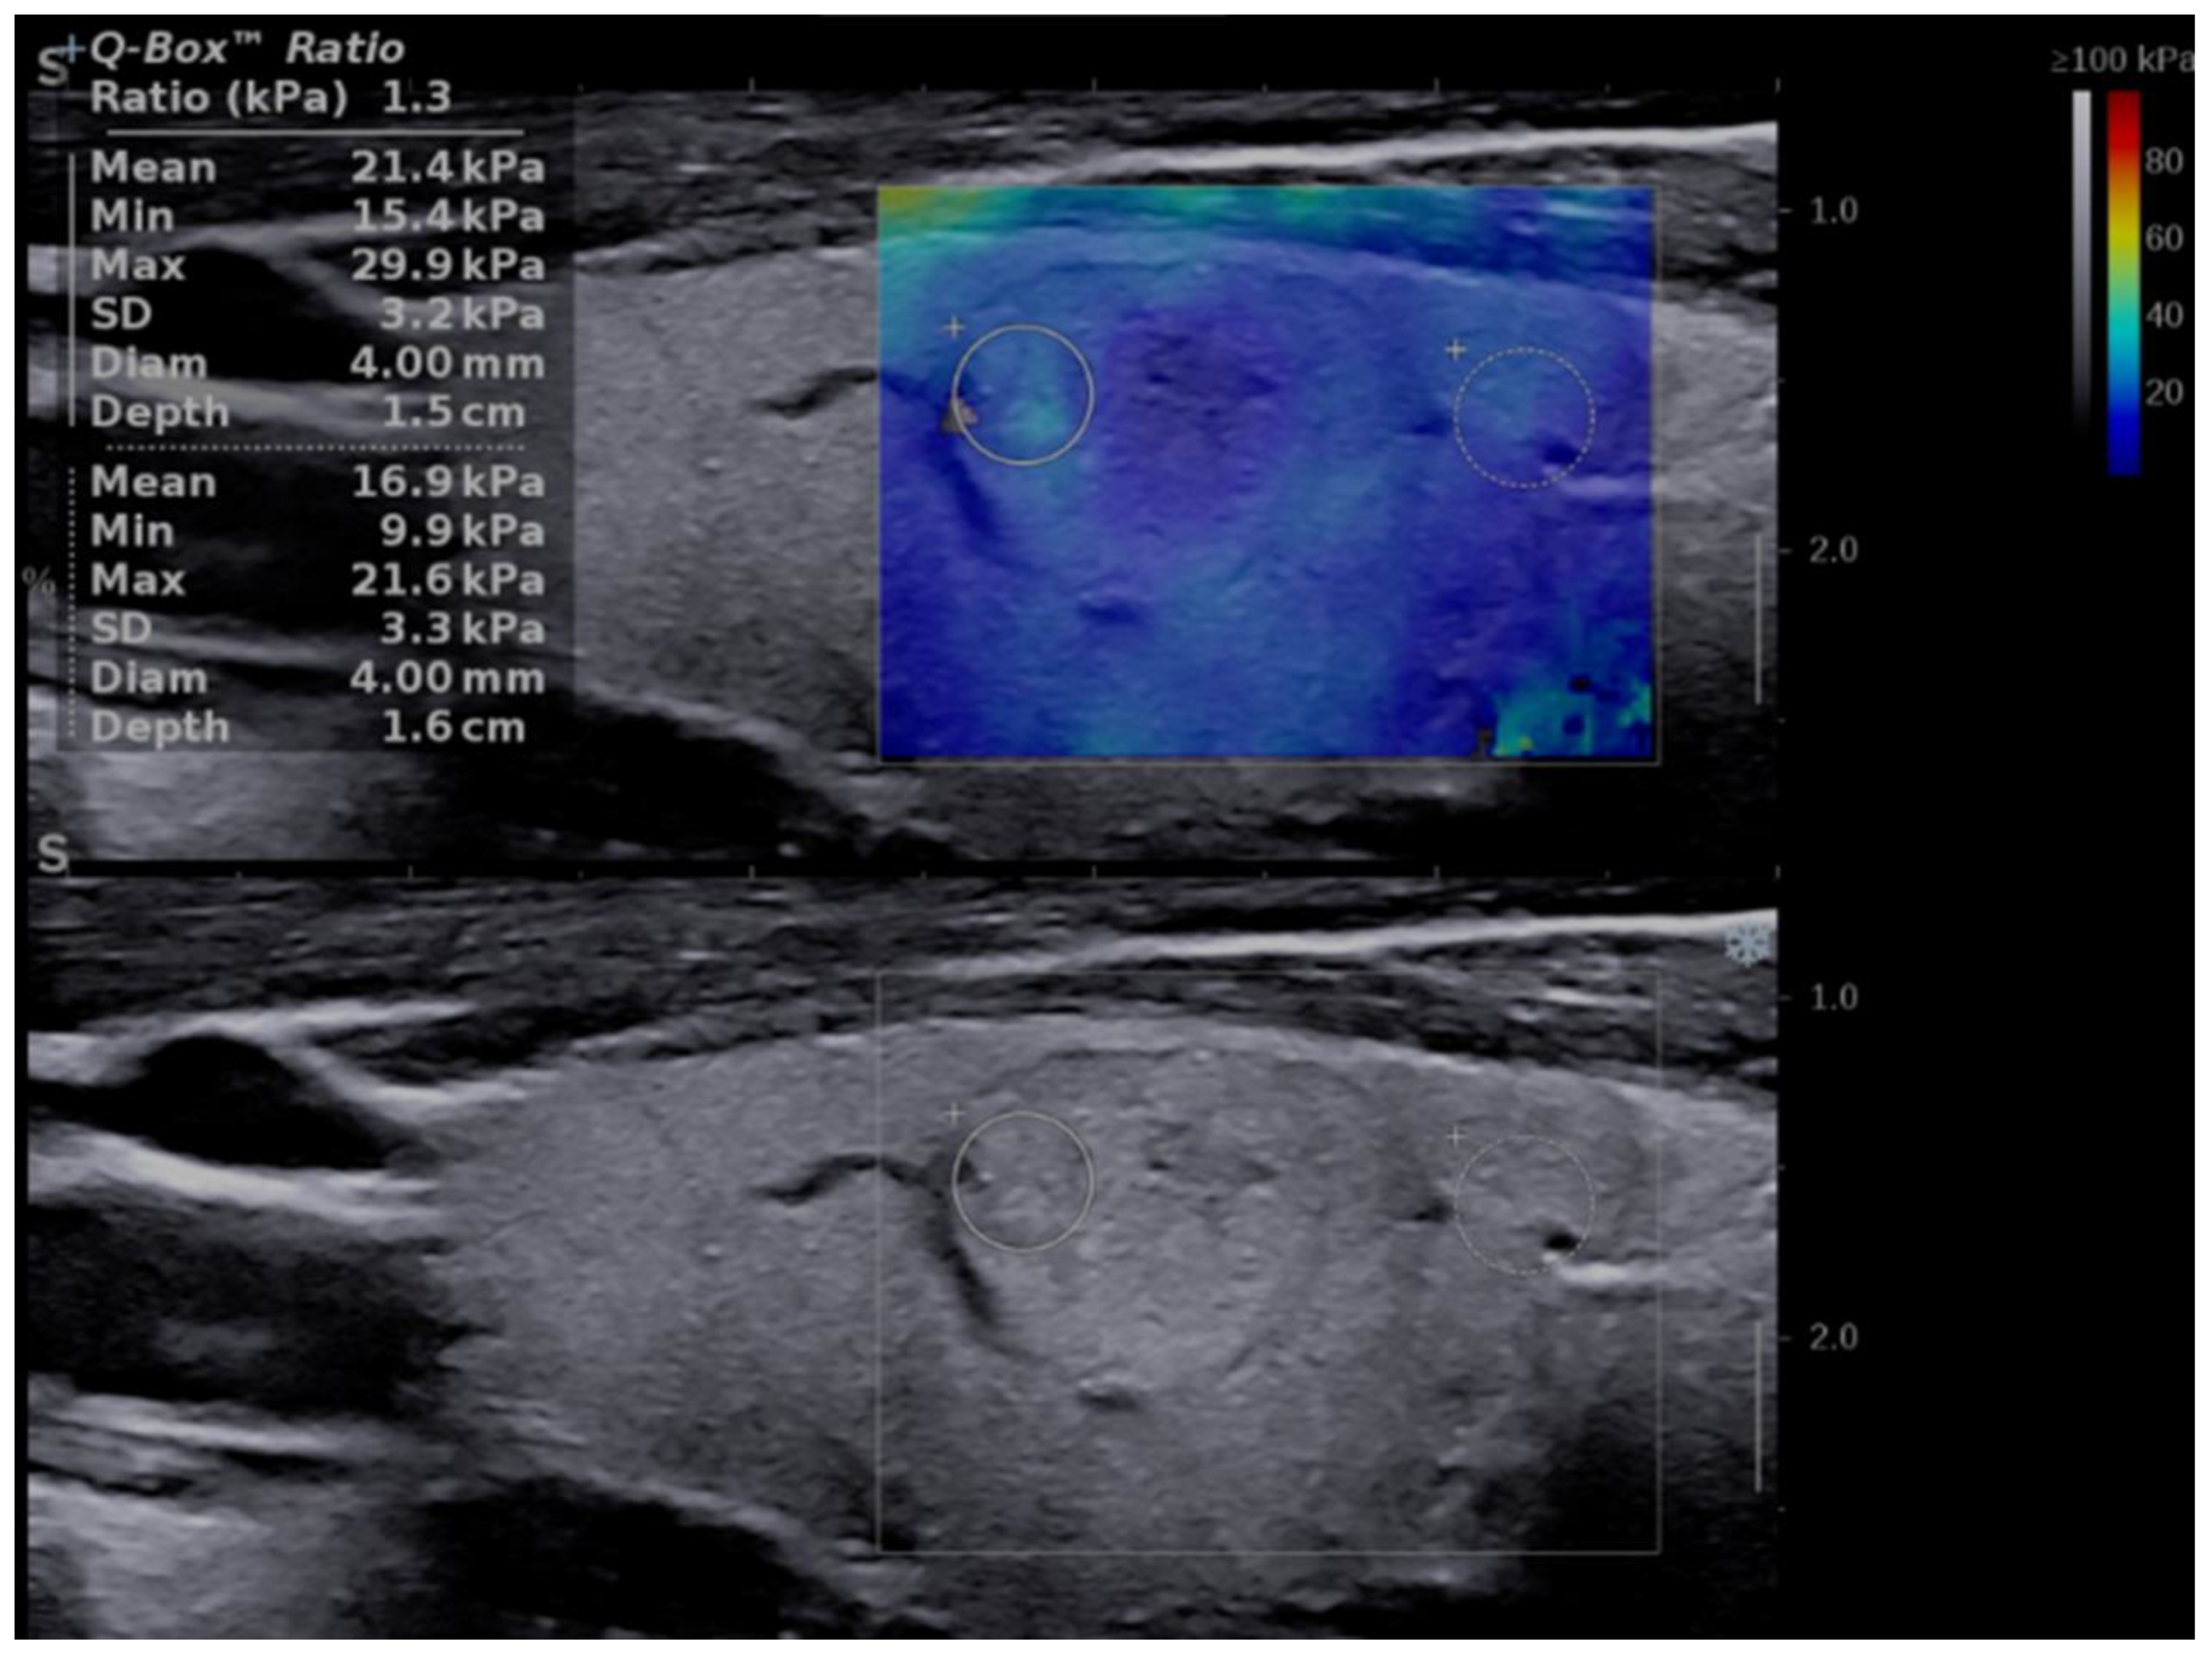

Figure 9 illustrates the elasticity images of a thyroid nodule with a low risk in 2B that appeared soft in both SE (a) and SWE (b) and was revealed by the pathology report to be a classic variant of a papillary thyroid cancer.

Figure 9.

False-negative elastography result in a multifocal PTC case. Entirely soft nodule in both shear-wave elastography (a): Mean elasticity index = 9.3 kPa; and strain elastography (b): strain ratio = 1.14.